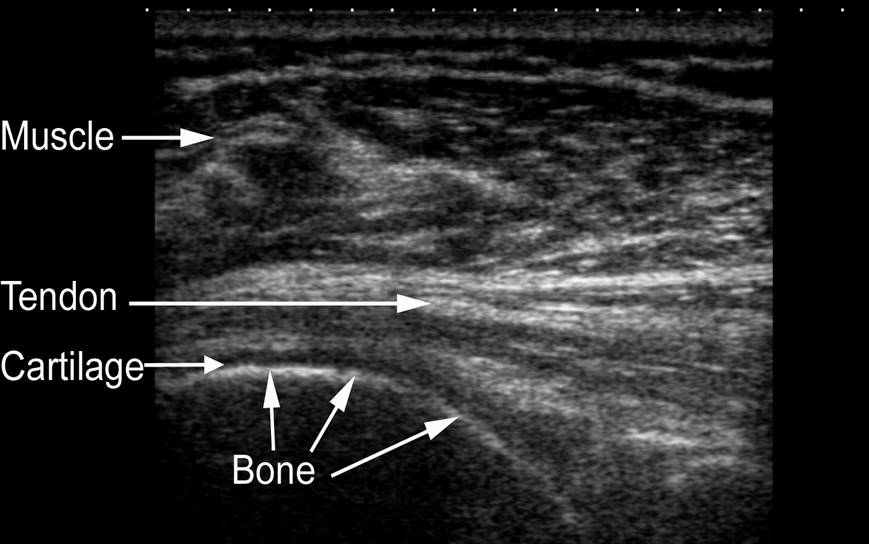

Ultrasound

Ultrasound don’t use radiation to take images. They use sound waves to make images from the echoes.

It’s a very safe and painless way to get a look inside, which is why it’s used to see babies inside their mummy’s tummies.

A squidgy gel is put on to your skin, so that a probe (that looks a bit like the hand held scanners you might use in a supermarket) is able to move smoothly across your skin and to ensure that there is continuous contact for the ultrasound waves to pass through.

The probe is connected to a computer and a monitor. Pulses of ultrasound are sent from the probe through your skin and into your body. Ultrasound waves are bounced back from the structures of the body and are displayed as an image on the monitor. As well as producing still pictures, an ultrasound scan shows movement that can be recorded on to video.